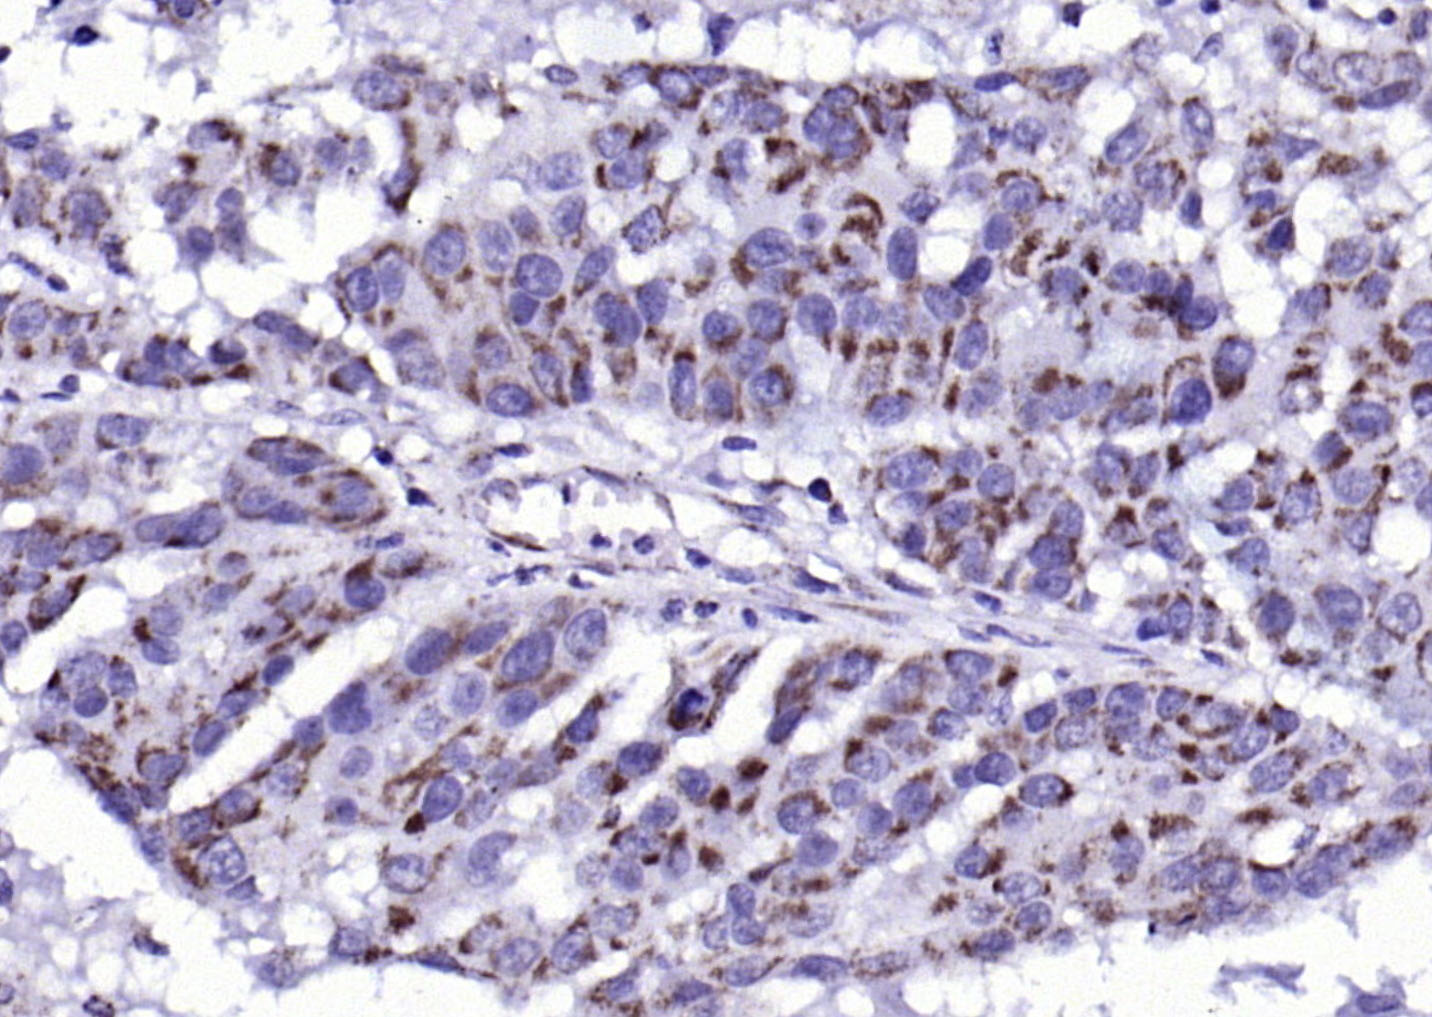

| 产品应用 | IHC-P=1:100-500, IHC-F=1:100-500, IF=1:100-500, Flow-Cyt=3ug/Test Not yet tested in other applications. |

| {IHC-P} | {1:100-500} |